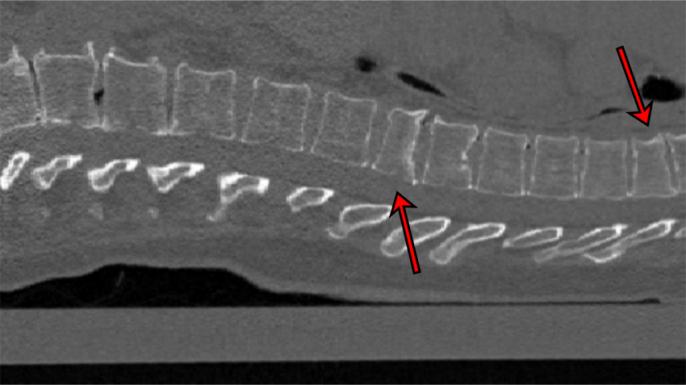

最近的一个例子是,经过训练的人工智能可以识别小骨折,表明患者患有骨质疏松症。如果及早发现,患者可以采取措施加强骨骼。通常,这种疾病要在痛苦的、可能致残的骨折后才能被诊断出来。

这种由德国研究人员开发的新人工智能,可以在出于其他原因(如检查患者肺部)而进行的计算机断层扫描(CT)中寻找表明骨质疏松症的小骨折,并对其严重程度进行分级。

“我们的程序可以在这样的检查中在后台运行,”主要研究者 Eren Yilmaz 说。“它自动检查脊柱,并对任何可能在其他情况下未被发现的椎体骨折给出指示。”

该团队在 159 张脊柱的 CT 扫描上对该 AI 进行了测试,该 AI 总共发现 170 处骨折,并正确分类了 90% 的骨折扫描和 87% 的无骨折扫描。这种人工智能仍在开发中,但 Yilmaz 说,如果它能进入常规放射学,它可能是“预防骨质疏松症严重后果的早期预警系统”。